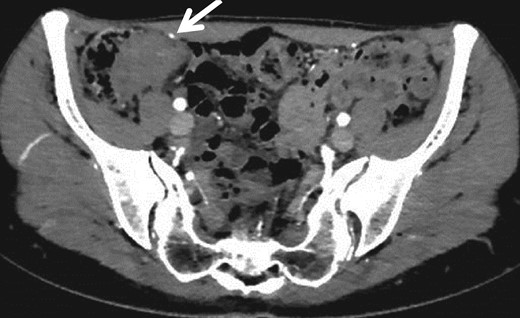

A 30-year-old woman underwent left ovariectomy and right ovarian endometrioma resection. At 40 years old, she noticed hematochezia and right-lower abdominal pain during menstruation, the symptoms continued over 3 years. At 43 years old, although she no longer noticed the same symptoms, she had right-side chest and back pain during menstruation so visited the doctor. A tumor of the ileocecum and right pneumothorax were discovered by computed tomography (CT). Pneumothorax was improved by conservative treatment. Submucosal tumor (SMT) was discovered at the rectosigmoid (RS) by colonoscopy (CS). The patient was referred to our hospital. A 3 cm size mass was discovered in the right-lower abdomen. Rectal examination was unremarkable and laboratory data was normal. CS showed the SMT with erosion at RS (Fig. 1a). As the scope could not pass through the sigmoid colon, we used the double balloon endoscopy. We observed erythrogenic mucosa of the ileum resembling salmon roe (Fig. 1b), and the cecum was suppressed from the outside. Biopsy was taken from the RS and ileum, but the pathological result was benign. Endoscopic ultrasound guided fine needle aspiration was also performed from the RS, but no abnormal cell were observed. By abdominal CT, a mass lesion was recognized at the ileocecum. No abnormal lesions were recognized at the rectum (Fig. 2).

Specimen: Strong dimpling of the serosa on rectum and ileocecum was recognized (Figs 3a, b and 4a, b).